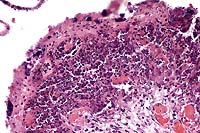

This rabbit had severe necrotizing metritis due to bacterial

infection of the uterus with Staphylococcus aureus. Numerous bacterial

colonies consistent with Staph. were present in the affected uterine

mucosa, and culture of the uterus yielded pure growth of Staphylococcus

aureus.

Conference Note: A gram-stained section viewed in conference confirmed that the cocci are gram-positive. Participants also viewed additional histologic sections from this case, including sections of placenta and fetal lung. The placenta was diffusely necrotic, and there were numerous colonies of cocci within the placenta and mesometrium, and within several fetal bronchioles. The latter finding suggests that there was periparturient fetal distress, with aspiration of placental fluid.